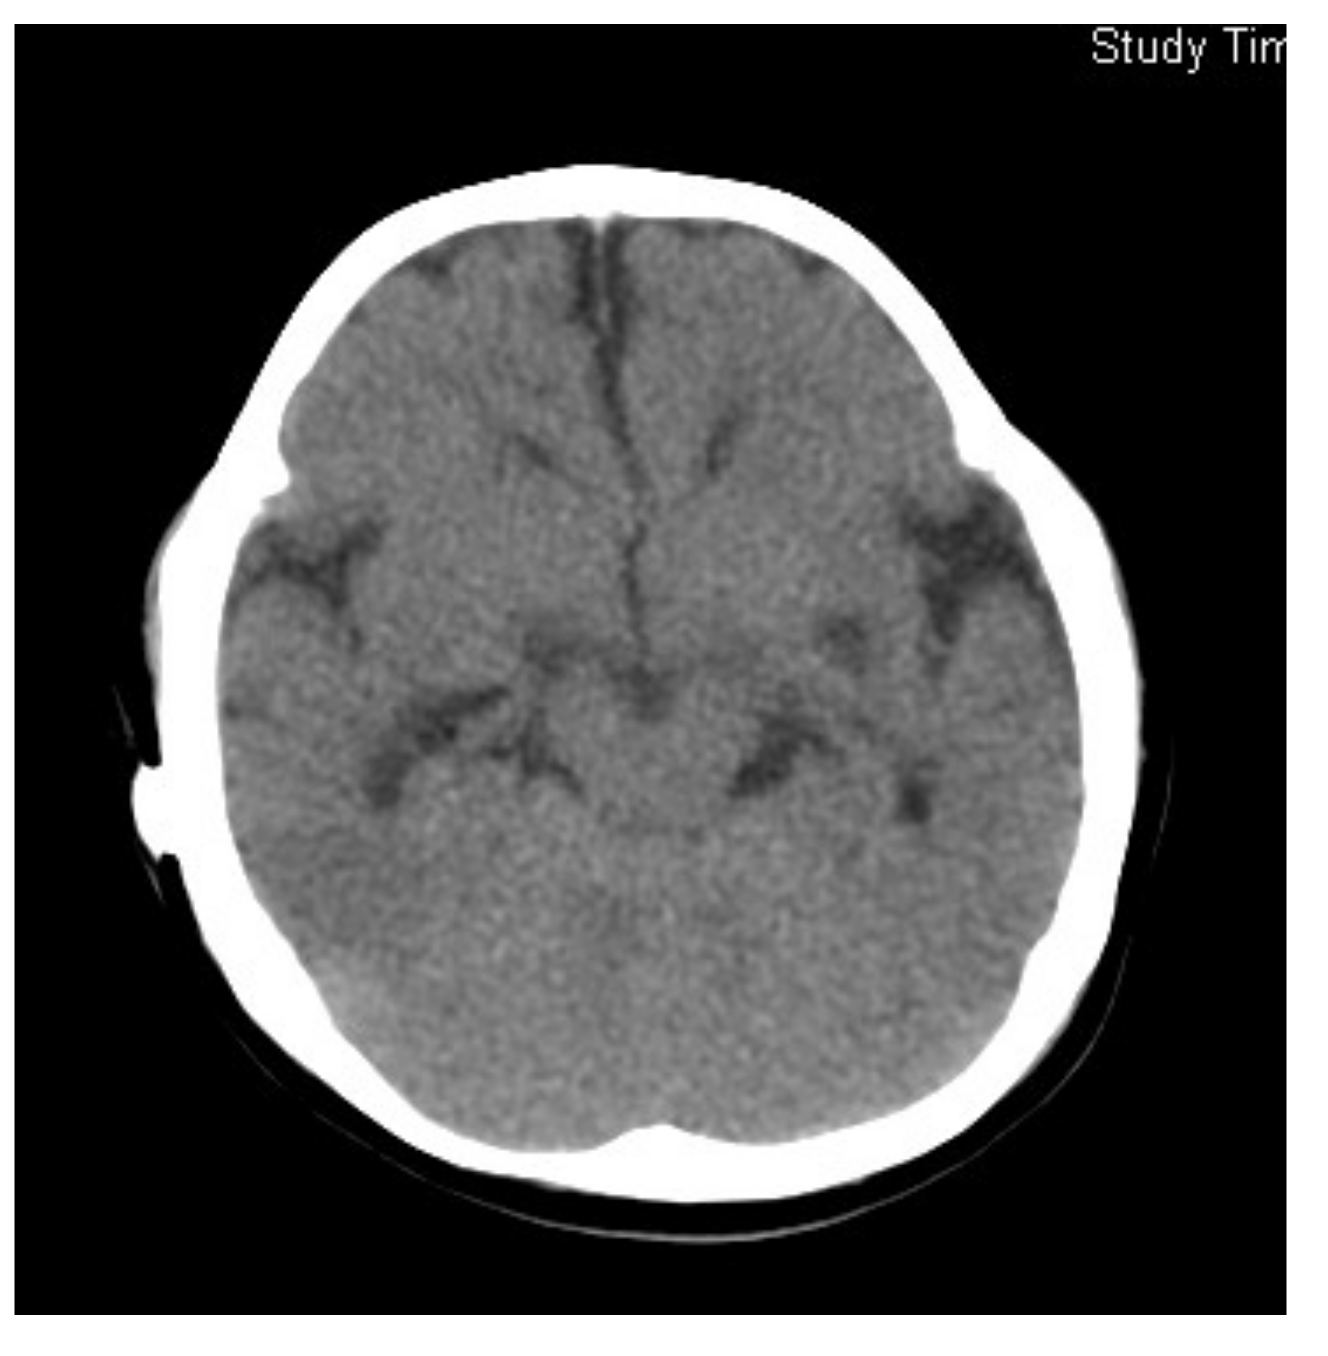

Figure 3.

Brain CT of Case 2 at 12 months of age, 7 months after starting betaine treatment.

The administration of betaine monohydrate (100 mg/kg/day) was started at 4 months of age, and her respiratory status and vitality improved rapidly. Sanger sequencing of the methylenetetrahydrofolate reductase gene (MTHFR) detected a homozygous variant, c.466_467GC > TT, and both parents were found to be heterozygous carriers of this variant. Based on the diagnosis of homocystinuria type III caused by MTHFR deficiency, betaine therapy was continued at the dosage of 300 mg/kg/day, which raised plasma Met levels to 14–40 μmol/L, and reduced plasma tHcy concentrations to 50–110 μmol/L. Head MRI at the age of 12 months revealed the almost complete resolution of ventricular enlargement and atrophic changes (Figure 3). However, severe psychomotor retardation became evident, with a development quotient of 36 at the age of 1 year and 4 months. Epileptic seizures also appeared at the age of 3 years, so the administration of sodium valproate was added. This case was reported previously [9].